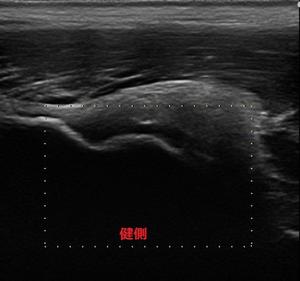

下前腸骨棘健側.jpg下前腸骨棘患側.jpg結果、下前腸骨棘付近、大腿直筋起始部の炎症と判明。